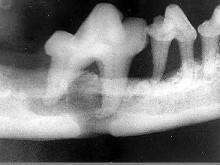

问题 颌面外伤患者,咬合错乱,下唇麻木张口受限,经X?线检查如图。应该为()

选项 A.上颌骨骨折 B.颧骨骨折 C.颧弓骨折 D.下颌骨骨折 E.牙槽突骨折

答案 D